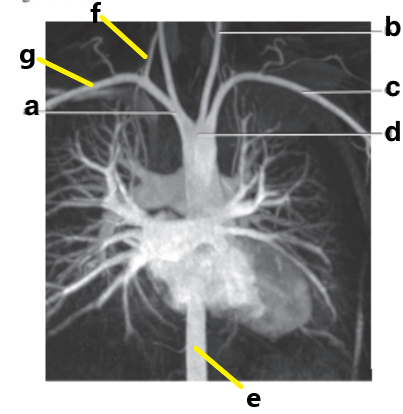

Which letter is the Left common carotid ?

b

Which letter is the left subclavian artery ?

Which letter is the Right common carotid artery ?

d

What is letter a ?

Brachiocephalic trunk

Which letter is the Descending aorta ?

f

Which letter is the right subclavian artery ?

g

c